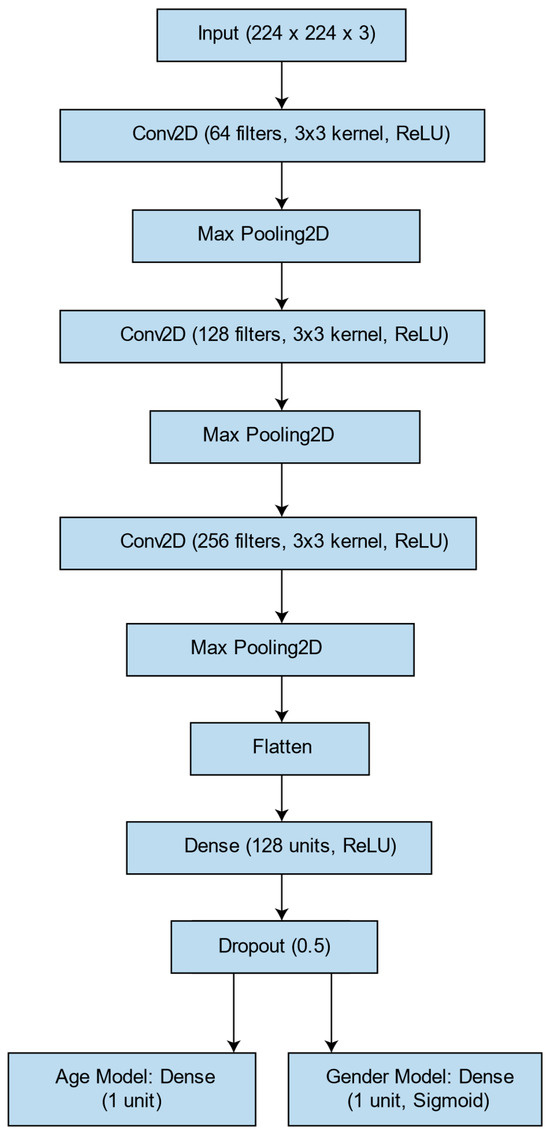

英文标题: Estimating Age and Sex from Dental Panoramic Radiographs Using Neural Networks and Vision–Language Models

中文标题:利用神经网络及视觉语言模型从牙科全景X光片推断年龄与性别

文章链接:https://www.mdpi.com/2673-6373/5/1/3